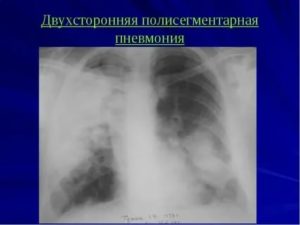

Двухсторонняя полисегментарная пневмония — опасное состояние, которое чаще всего возникает при несвоевременной диагностике одностороннего процесса и развивается как осложнение его.

Клиническая картина этой формы воспаления отличается тяжестью состояния больного, обусловленной значительным интоксикационным синдромом и выраженной дыхательной недостаточностью.

Общий анализ крови при пневмонии показывает наличие лейкоцитоза со сдвигом лейкоформулы влево, повышение СОЭ. Рентгенологическое исследование при полисегментарной пневмонии выявляет очаги инфильтрации (затемнения) в нескольких сегментах одного или двух легких.

Двухсторонняя полисегментарная пневмония – это одно из самых тяжелых заболеваний нижних дыхательных путей. Она затрагивает сразу много участков, или же сегментов ткани лёгкого.

В этом конкретном случае воспалительный процесс затрагивает оба лёгких, он требует длительного и сложного лечения. Чаще всего, оно развивается у людей с пониженным иммунитетом или у детей первого года жизни.

Двухстронняя полисегментарная пневмония – это недуг, при котором воспаление затрагивает сразу несколько участков тканей обоих лёгких, называемых сегментами.

Диагноз «двухсторонняя полисегментная пневмония» ставится по клиническим симптомам и результатам рентгенографии грудной клетки. Дополнительно необходимо сделать общий анализ крови, для того чтобы определить возбудителя болезни.